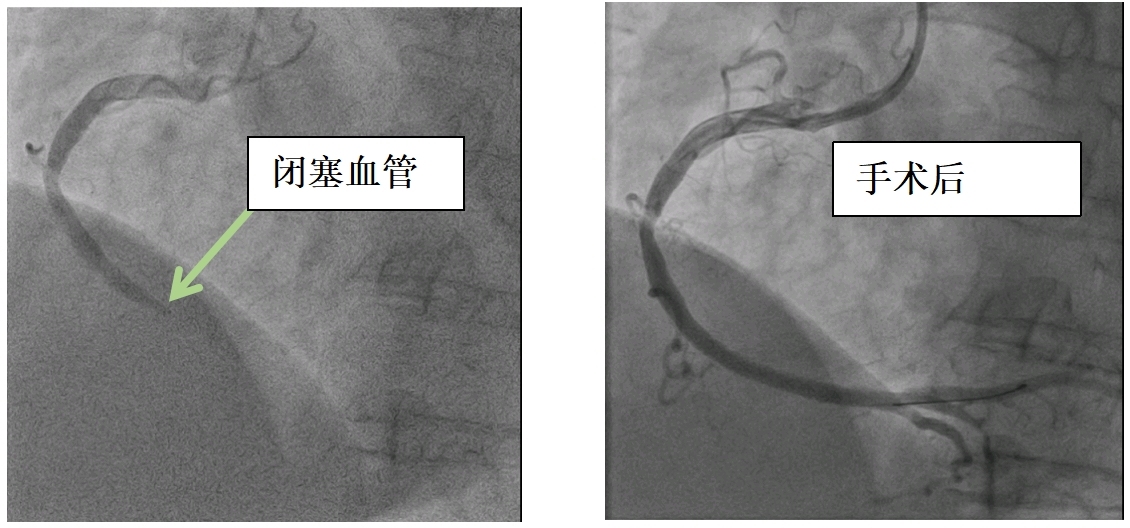

聂女士右冠状动脉图像。